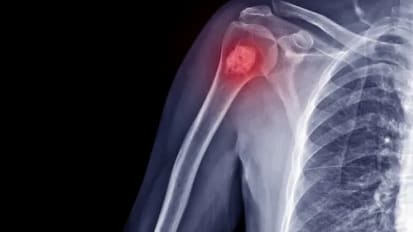

Ortho-oncology: Improving care for patients with metastatic bone disease

Advancements in medical oncology over the last decade have created a paradigm shift in MBD care, transitioning toward a more hopeful model focused on managing metastatic cancer by keeping patients active and mobile.